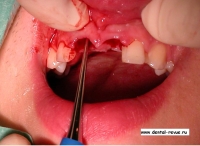

4. Рассечение круговой связки перитомом.

5. Удаление зуба.

6. Кюретаж, контроль сохранности вестибулярной стенки лунки.